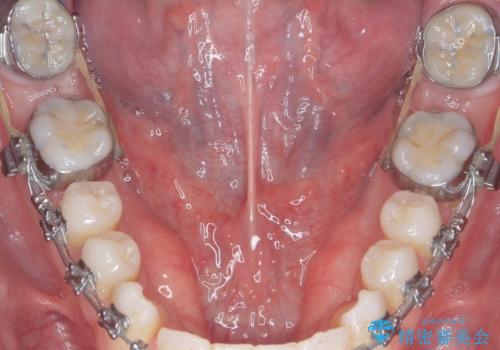

舌小帯の切除

- 30代男性

- 他院で矯正治療をしているが、滑舌も気になるため舌小帯の切除を希望し来院されました。